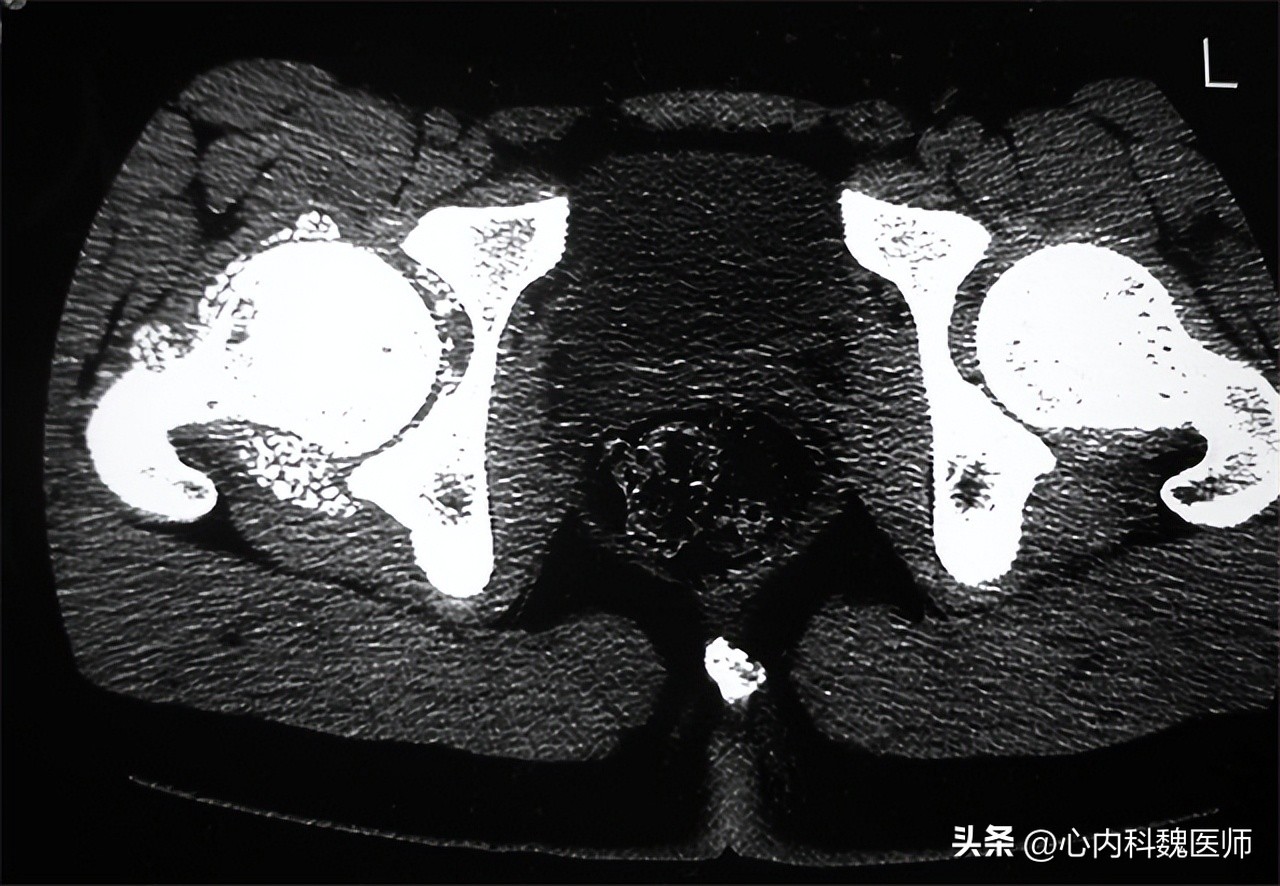

股骨头坏死 早期患者主要表现为疼痛,常见于髋部、腹股沟区等部位 ,因此出现胯骨疼痛时,有可能是股骨头坏死。疼痛逐渐延伸并加重,放射到臀部、大腿、膝关节等部位。如果不及时进行治疗,患者会逐渐出现行走困难、间歇性跛行、功能障碍等,严重的患者疼痛剧烈,无法行走。

股骨头坏死使用药物治疗时,效果多不明显,只能起到延缓病情发展的作用。患 者一般采用手术治疗 ,保髋手术,通过修复髋关节功能,使股骨头内的血供恢复正常。还有一种就是现在很常见的 人工关节置换术 ,对于股骨头严重坏死的患者或是治疗效果不好的患者建议选择人工关节置换术。